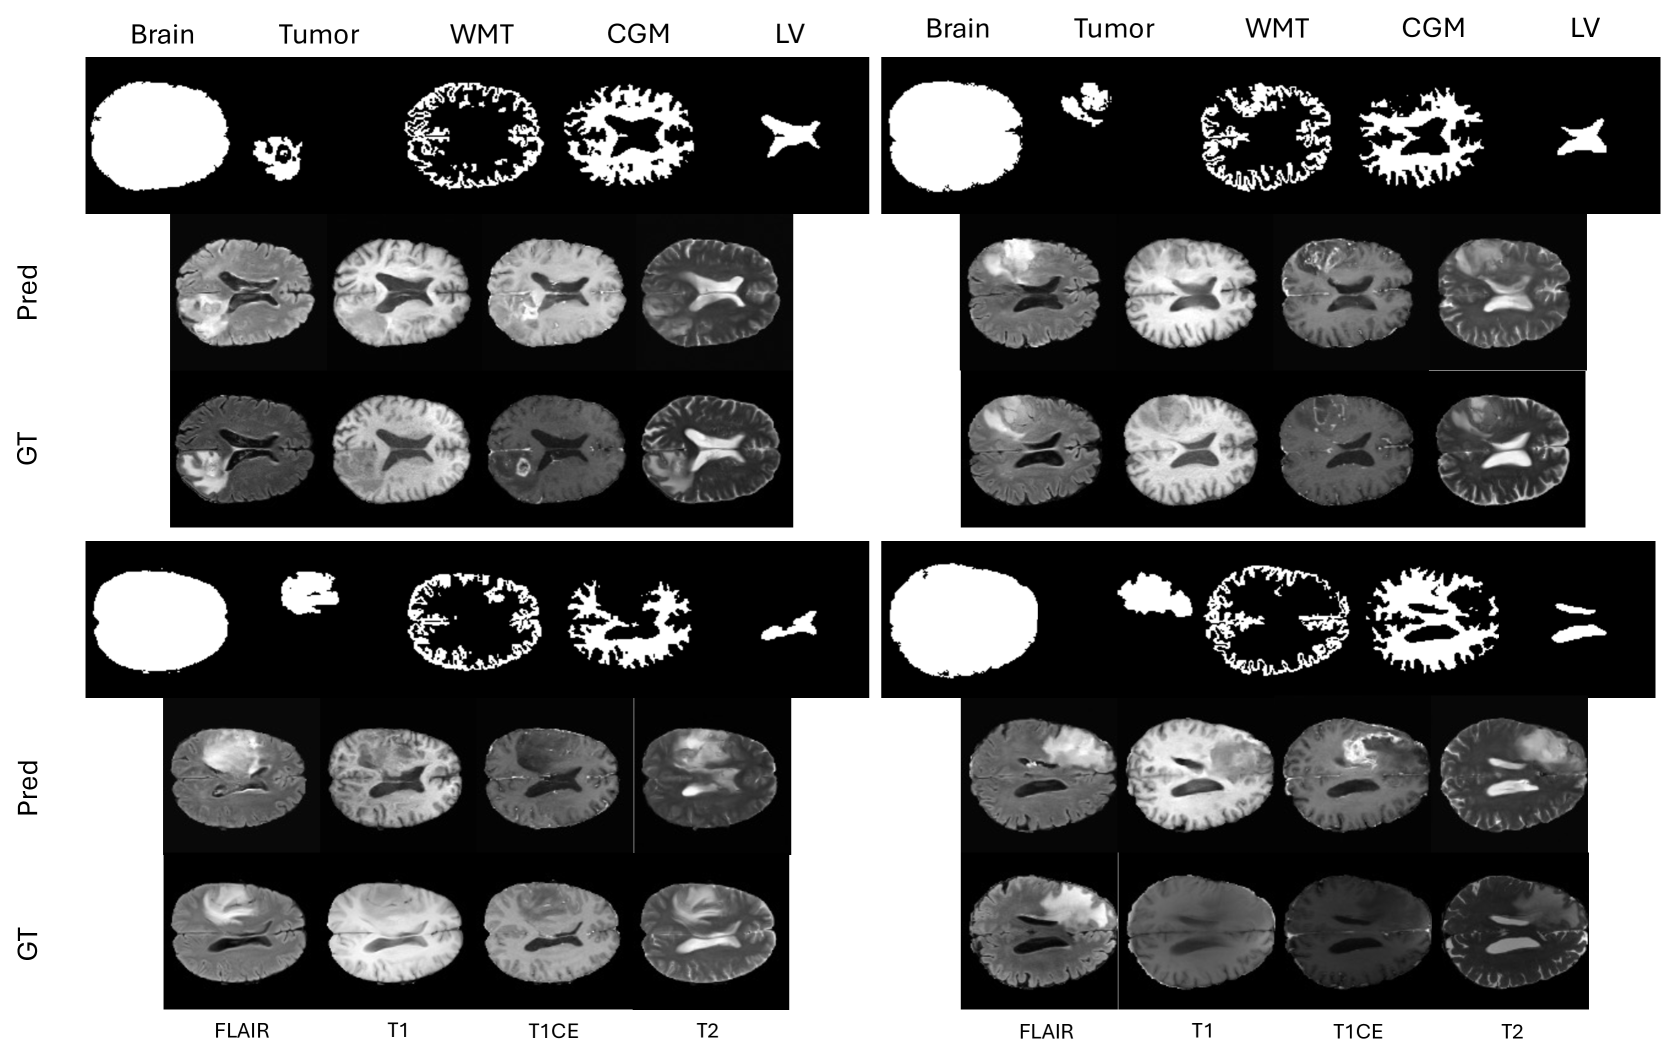

Brain anatomy. In addition to the tumor, we use several other anatomically important structures namely White Matter Tracts (WMT), Cortical gray Matter (CGM), Lateral Ventricles (LV), and Brain Masks (BM). The detailed explanation about the generation of the structures are discussed in Sec. 4.1. In Fig. 3, we show examples of the different structures. More examples are shown in Supplementary (Figure 10).

For qualitative analysis, we compared the images generated by BrainMRDiff with those produced by different baseline models. In Fig. 6, we show a comparison of generated images from DDPM, ControlNet trained with BM, ControlNet trained with tumor segmentations, and BrainMRDiff, alondside the corresponding real FLAIR sequence from the BraTS-AG dataset. Neuroradiologist’s (8 years exp) interpretation: We observe that since DDPM lacks anatomical controls, it generates visually plausible MRI sequences but fails to preserve anatomical structures. In contrast, ControlNet introduces anatomical awareness, but its performance remains suboptimal in accurately capturing both brain and tumor morphology. BrainMRDiff, however, achieves superior fidelity by preserving both brain anatomical details and tumor topology, resulting in highly realistic and anatomically coherent MRI sequences. In Fig. 7, we further illustrate real and BrainMRDiff-generated images along with the corresponding anatomical masks for two cases from the BraTS-AG dataset, showcasing our methods ability to generate high-quality and anatomically-accurate images. More examples are provided in the Supp. (Figs 9 and 11).